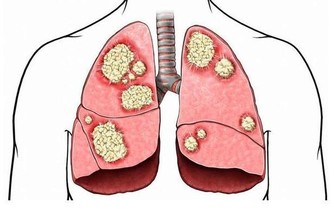

糖除了會增加熱量,還會為肝臟增添負擔。研究人員發現,含糖豐富的飲食與血液和肝臟中的脂肪含量升高有一定的關聯。不止一項研究表明攝入大量糖分會改變脂肪代謝,從而增加患心血管疾病的風險。肝臟中有過多的脂肪堆積是不健康的,高脂肪的人群中有大部分的人患有非酒精性脂肪肝。

結果發現,高糖飲食的非酒精性脂肪肝患者脂肪代謝過程發生了變化,這些變化帶來的後果是患心髒病或者中風的風險更大了。原本肝臟脂肪含量較低的男性在一段時期的高糖飲食過後,肝臟脂肪含量有所升高,其體內脂肪代謝發生了類似於非酒精脂肪肝患者的變化。研究得出的結論是,攝入過量的糖會改變脂肪代謝,增加患心髒病的風險,即使只是一小勺糖,只要超過了正常攝入量,對人的影響就可能是致命的。

目前,非酒精脂肪肝的患病率在兒童和成人中都有所上升。兒童和青少年更喜歡碳酸飲料和糖果,糖的攝入量也很容易超標,考慮到兒童和青少年中非酒精脂肪肝的高患病率,我們要引起對年輕人群未來健康的關注。